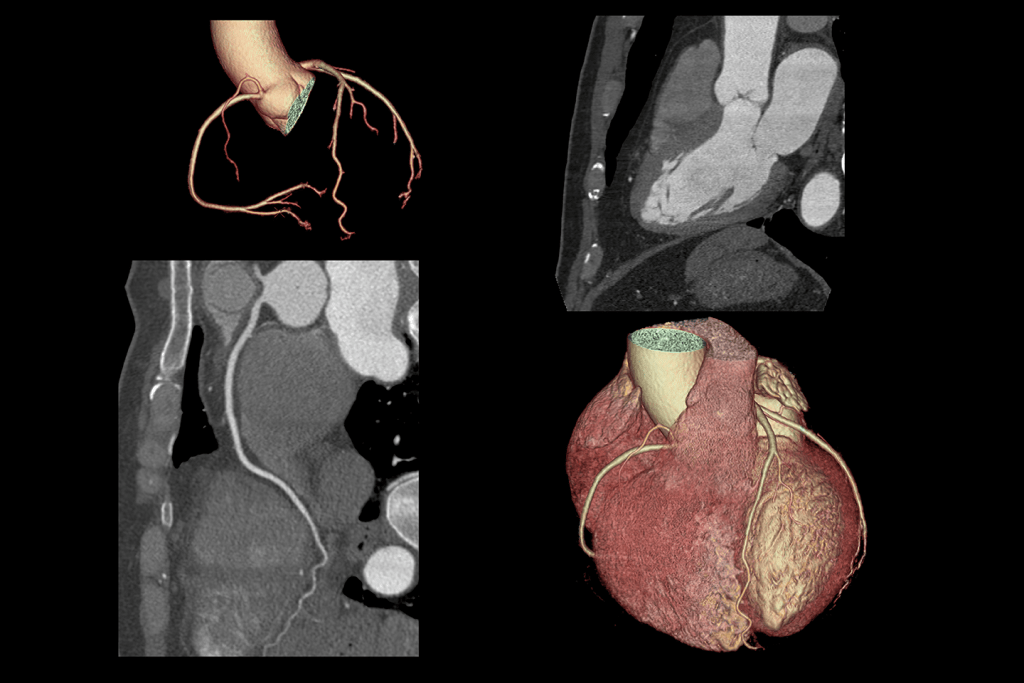

سی تی آنژیوگرافی عروق کرونر یک روش تصویربرداری غیرتهاجمی و پیشرفته از عروق قلب است که با استفاده از اشعه ایکس و ماده حاجب حاوی ید، تصاویر سه بعدی دقیق از شریانهای کرونر ایجاد می کند. این روش به پزشکان کمک می کند تنگیها، انسدادها و پلاکهای چربی یا کلسیم در عروق قلب را شناسایی کنند.

سی تی آنژیوگرافی عروق کرونر یکی از زیرمجموعههای سی تی اسکن قلب محسوب می شود و نسبت به آنژیوگرافی سنتی مزایایی چون سرعت بالا، غیرتهاجمی بودن و امکان انجام در افرادی با وسایل پزشکی کاشته شده دارد.

- تصاویر سه بعدی دقیق: امکان تشخیص تنگی ها، انسدادها و پلاک های عروقی با وضوح بالا و ارزیابی آناتومی قلب فراهم میشود.